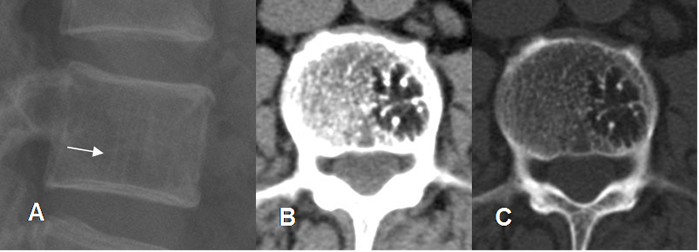

Fig 150. Hemangioma óseo.

A: Rx lateral, B: TAC axial en ventana de tejido y C: en ventana osea. Area radiolúcida con signo de la empalizada, secundario al engrosamiento de la trabeculación vertical y puntos escleróticos rodeados por grasa en el TAC, por hemangioma óseo.